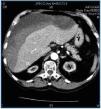

Patients on periodic HD have an elevated risk of spontaneous haemorrhages or haemorrhages caused by minimal trauma to the retroperitoneal, renal, pericardial, mediastinic and subdural areas. Multiple factors affect predisposition to bleeding, including platelet dysfunction, antiplatelet agents and anticoagulants.1,2 The development of a subcapsular hepatic haematoma is an exceptional complication that can occur spontaneously or with minimal closed trauma.3,4 We present a patient aged 77 years who in 2003 was diagnosed with chronic kidney disease second to myeloma kidney (IgG Kappa). Treatment with melfalan/prednisone decreased the circulating paraprotein and improved the medullar affectation. In February 2004, the patient began HD. During the last two years, the patient received two cycles of melfalan/prednisone, and later, bortezomib (Velcade®). He remained stable, with the disease under control and without anaemia with EPO. From April to July 2006, he received conjugated oestrogen (Equin®) (20mg/day) for uraemic thrombopathy. Lately, the patient has been taking aspirin as an anti-platelet agent. On 7 August 2006, eight hours after finishing the HD session, he experienced dizziness and fell, striking his right hypochondrium, and lost consciousness for several minutes. When he was admitted to the hospital he was conscious and aware of his surroundings; he complained of pain in his right scapula. Blood pressure was 55/35, cardiac frequency 72l/min and he showed sinus rhythm. Analytical tests showed: haematocrit 19%, haemoglobin 6.9g/dl, 300,000 platelets/mm3, 10,000 leukocytes/mm3 with the normal formula, PT 82%, INR 1.2 and fibrinogen 520mg/dl. Other data: Na 139mmol/l, K 6.7mmol/l, HCO3 22mmol/l, urea 84mg/dl, Cr 7.5mg/dl, GGT 727UI/l, GOT 127UI/l, GPT 167UI/l, LDH 372UI/l and total bilirubin 0.4mg/dl. A thoracic-abdominal CT with contrast revealed a subcapsular hepatic haematoma measuring 10 x 7 x 20cm in the right lobe; the organ was displaced, but without underlying hepatic lesions (figure 1). The kidneys were atrophic and there was a moderate amount of free liquid (blood) in the pouch of Douglas. To reverse the hypovolaemia, we administered isotonic saline and blood transfusions (four packs of red blood cells) and gum for the hyperpotasaemia. Six hours after being admitted, his haemodynamics were stable and he underwent an HD session without heparin. In the following 48 hours he remained at rest and under observation with frequent haematological checks.Haemoglobin levels remained stable. Local discomfort required mild analgesics.Over the following days, HD was performed under close monitoring and without heparin. Eight days after admission, during a CTexam, the haematoma had not increased in size and remained within the subcapsular area.The patient was referred to his original unit and follow-up by a series of CTs showed the slow, progressive reabsorption of the haematoma over eight weeks, with no need for surgery.

Figure 1.